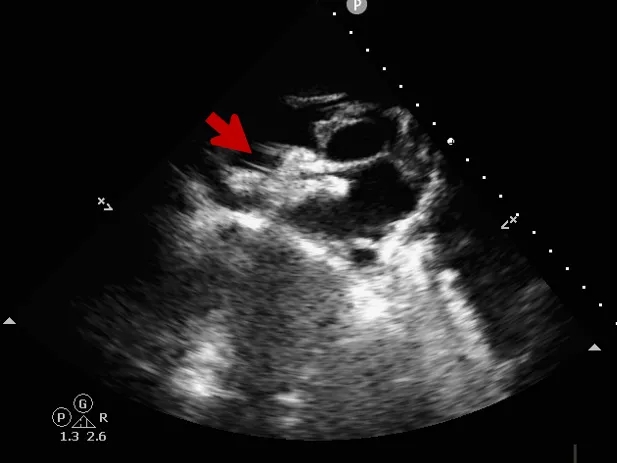

术前超声

超声描述:右房室较大,左房室不大。房间隔中部可见中断,约14x16mm。缺损边缘较硬,二尖瓣侧缘、后上缘分别为16mm、8mm,主动脉侧缘、后壁缘分别为0mm、10.7mm,上、下腔静脉侧缘分别为16、14mm。十字交叉存在。房间隔长度43mm。M型二尖瓣呈双峰,前后叶逆向,E-E间距相等。

CDFI:房水平可见一股红色彩流由左房经缺口进入右房。主动脉瓣下左室流出道探及微量舒张期反流信号。三尖瓣口右房侧探及微量收缩期反流信号,Vp 2.7m/s,PG 29mmHg。二尖瓣口左房侧探及微量收缩期反流信号。

术中复测

超声可见房间隔连续中断,彩色多普勒可见过隔血流

测量房间隔缺损直径最大为23.9mm,房间隔总长53.8mm